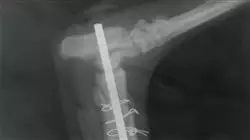

Este curso inclui 20 das Doenças Ortopédicas mais importantes que afetam os cães e os gatos, bem como informação especializada, teórica e prática para chegar a um diagnóstico correto. Desenvolva as caraterísticas mais importantes de cada uma destas doenças em relação à raça, ao sexo e à incidência na clínica veterinária.

Além disso, examine o historial clínico e forneça os métodos de diagnóstico mais úteis para interpretar as descobertas laboratoriais que podem ser relevantes e apoiar o exame radiográfico ou de ressonância magnética.

Finalmente, analise o que se observa na histologia, bem como todos os métodos que existem para chegar ao diagnóstico definitivo de cada uma destas doenças.